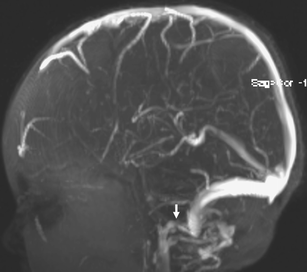

Fig. 3

Fig. 4